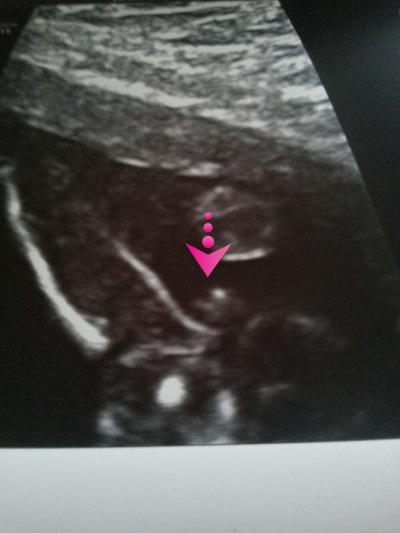

Nachdem mein baby vor 6 Wochen noch beides hätte sein können ist es mittlerweile 3 mal bestätigt ein Mädchen. Freu mich riesig ein Pärchen haben zu dürfen und mein Sohn bekommt seine gewünschte Schwester.  Ich häng noch das rätselbild an :-)

Bild zu Für alle die mitgeraten haben :-) - Schwanger - wer noch? Rund um die Schwangerschaft